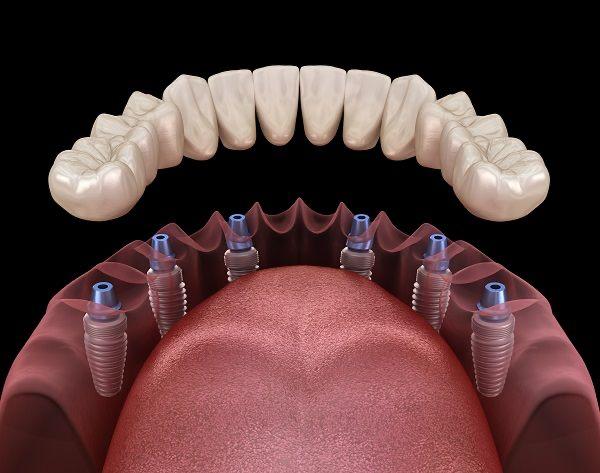

L'implant dentaire est un dispositif en titane ressemblant à une vis, qui sert de racine artificielle à une prothèse dentaire. Son rôle est de remplacer une dent manquante et d'assurer toutes les fonctions de la racine naturelle, en servant d'intermédiaire entre l'os de la mâchoire et la prothèse. Il permet la pose d'une prothèse amovible (dentier) ou d'une prothèse fixe (bridge, couronne, prothèse complète, etc.).

Les prothèses sur implants reposent sur des racines artificielles (implants) pour remplacer une ou plusieurs dents. Elles peuvent être fixes ou amovibles selon les besoins du patient, offrant un confort et une stabilité remarquables.